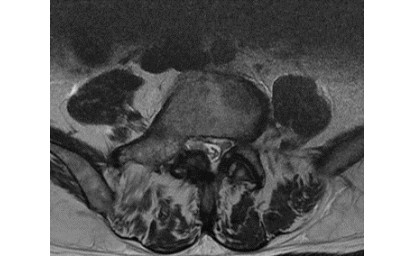

症例2:左腸腰筋膿瘍(70代男性)

単純CT及び単純MRIを実施しているが、病変を検出できなかった。

DWIBSで「腸腰筋膿瘍」を検出することができた症例。